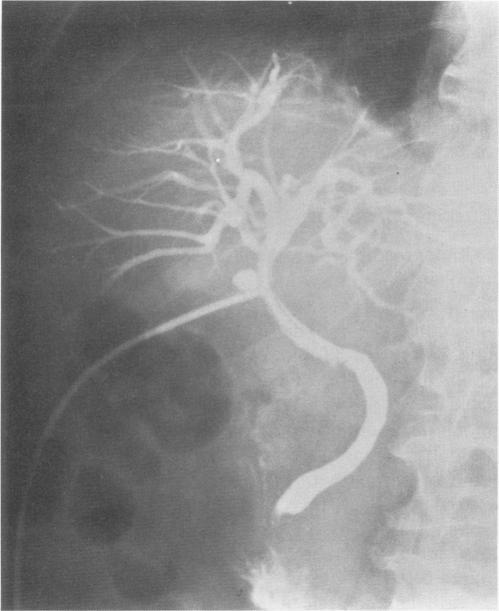

In this nonrandomized retrospective study, 101 patients with benign biliary strictures were included. Thirty-five patients were treated surgically and 66 by endoscopic stenting. Patient characteristics, initial trauma, previous repairs, and level of obstruction were comparable in both groups. Surgical therapy consisted of constructing a biliary-digestive anastomosis in normal ductal tissue. Endoscopic therapy consisted of placement of endoprostheses, with trimonthly elective exchange for a 1-year period.

RESULTS

Mean length of follow-up was 50 +/- 3.8 and 42 +/- 4.2 months for surgery and endoscopy, respectively. Early complications occurred more frequently in the surgically treated group (p < 0.03). Late complications during therapy, occurred only in the endoscopically treated group. In 46 patients, the endoprostheses were eventually removed. Recurrent stricturing occurred in 17% in both surgical and endoscopic patients.